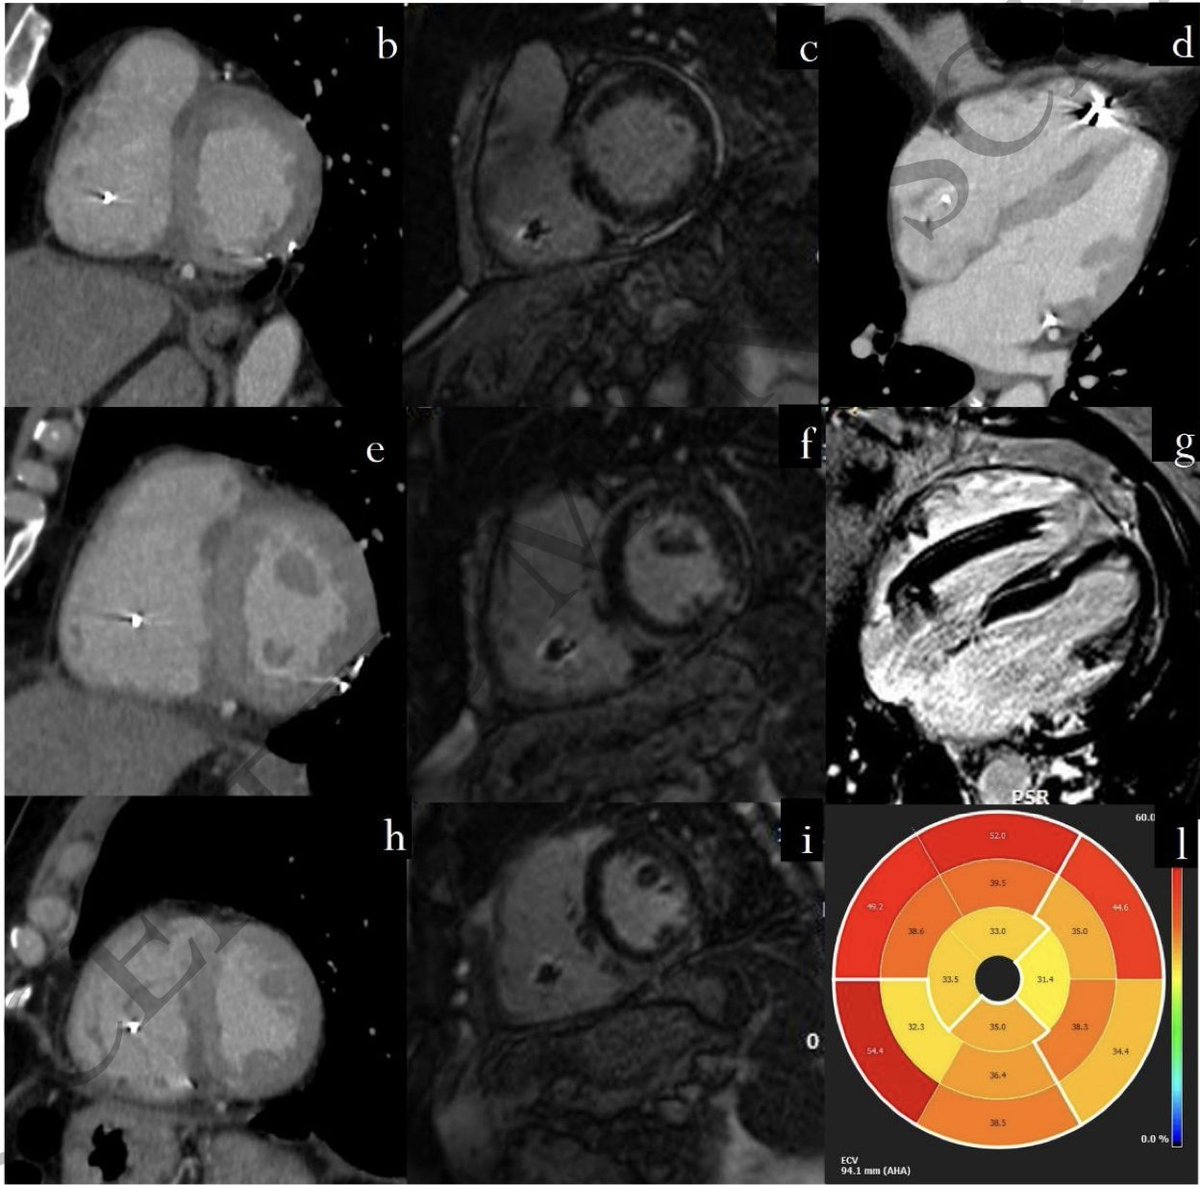

75 yo M presented late with Ant wall MI, echo suspected large contained rupture/ pseusoaneurysm confirmed on CT. Awaiting surgery @nicvd_karachi @alexsfelixecho #echofirst @iamritu @m_naeem_88 @Heart_SCCT @AJamilTajik @NicvdImaging #multimodalityimaging

SabhaBhatti's tweet image. 75 yo M presented late with Ant wall MI, echo suspected large contained rupture/ pseusoaneurysm confirmed on CT. Awaiting surgery